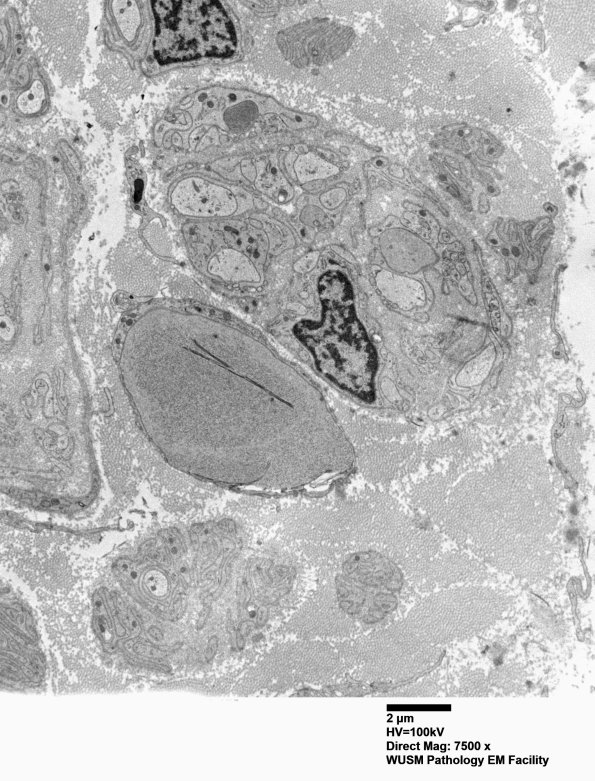

11L1,2 In these images delicate uncompacted tubulovesicular elements, dense axoplasm and a membranous cleft are illustrated. (electron micrographs)